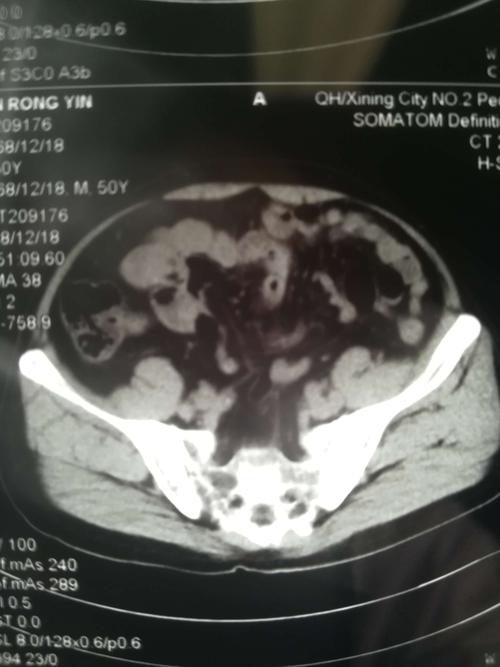

患者中老年男性,诊断:左侧腰疝